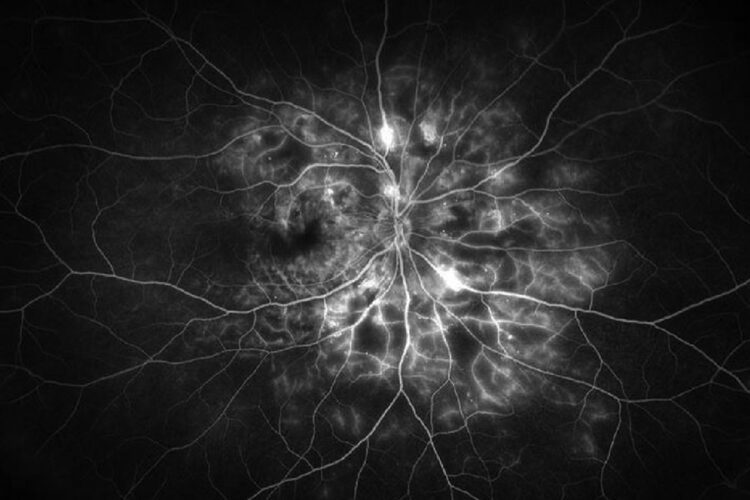

| Figura 1. Imágenes de un paciente varón de unos 30 años con diabetes tipo 2 mal controlada (hemoglobina A1c >12%) y sin atención ocular previa. La angiografía con fluoresceína en la cita inicial mostró áreas extensas de ausencia de perfusión periférica con frondas de neovascularización (se muestra el ojo izquierdo). La OCT mostró edema macular diabético grave que afecta al centro (arriba, a la derecha) que respondió bien a las inyecciones intravítreas de anti-VEGF (aflibercept) (abajo, a la derecha). Un año después de la presentación, tenía 20/20 en ambos ojos con una A1c <7% debido a una mejor adhesión al cuidado de la diabetes y un mejor control sistémico de la glucosa. Foto: Ian C. Han, MD. |